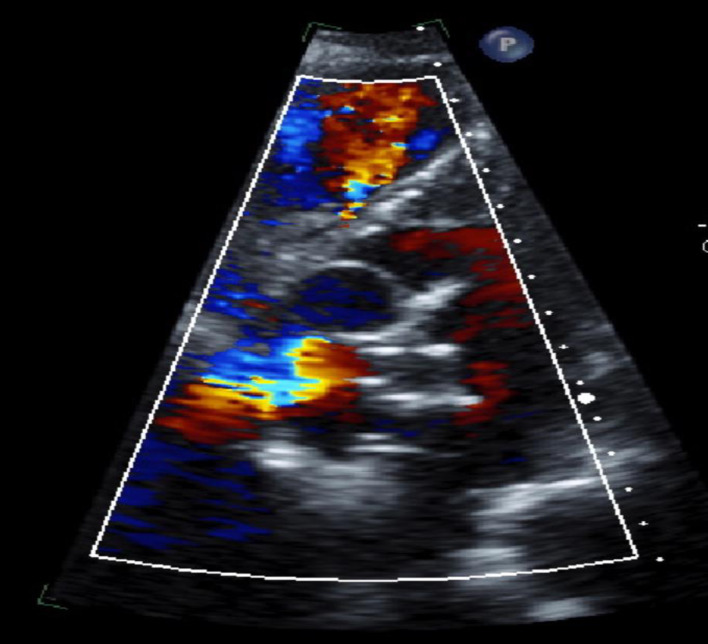

呼吸困难是一种令人痛苦的症状,表现为直立时呼吸困难,躺下时症状明显改善。与仰卧位时呼吸困难加重的正位性呼吸困难形成鲜明对比的是,POS 在从躺下到站立的过程中会出现血氧饱和度降低的独特症状。这种综合征症状微妙,给诊断带来了挑战,需要临床高度怀疑才能准确识别。在此,我们介绍了一例病史复杂的 79 岁女性患者,其主要病史包括深静脉血栓(DVT)和随后的肺栓塞(PE),需要长期服用华法林进行抗凝治疗;乳腺癌肿块切除术和化疗后病史;高血压和慢性肾脏疾病(CKD)。患者因持续低氧血症和提示 POS 的临床特征从一家生活机构入院。尽管进行了全面的体格检查和常规实验室检查,但未发现明显异常。然而,超声心动图检查发现了严重的卵圆孔未闭(PFO)和右向左分流,证实了 POS 的诊断。随后,医生使用 GORE CARDIOFORM 室间隔封堵器对 PFO 进行了经皮封堵,透视检查证实封堵器成功置入了房间隔内。值得注意的是,患者术后的氧合情况明显改善,并在两天内出院。POS 虽然罕见,但由于其可能导致相当高的发病率和死亡率,因此具有重要的临床意义。POS 的病理生理学基础在于肺血流和全身血流之间的不协调,最终导致患者在采取直立姿势时出现动脉饱和度降低。及时识别和干预对于减轻症状负担和避免相关并发症的恶化至关重要。早期诊断有助于实施有针对性的治疗策略,从而缓解呼吸困难,防止该综合征引发不良后遗症。因此,提高医护人员对 POS 细微表现的认识对于加快适当的管理和优化患者预后至关重要。

Platypnea-orthodeoxia syndrome (POS) is an uncommon yet clinically significant medical phenomenon characterized by dyspnea, a distressing symptom manifesting as breathlessness upon assuming an upright position, which notably improves upon reclining. In stark contrast to orthopnea, where dyspnea worsens in a supine position, POS uniquely presents with decreased blood oxygen saturation upon transitioning from lying down to standing up. This syndrome poses diagnostic challenges due to its subtle symptomatology and requires a high index of clinical suspicion for accurate identification. Herein, we present a case of a 79-year-old female with a complex medical history, notably encompassing deep vein thrombosis (DVT) and subsequent pulmonary embolism (PE) necessitating long-term anticoagulation with warfarin, a history of breast cancer status post lumpectomy and chemotherapy, hypertension, and chronic kidney disease (CKD). The patient was admitted from a living facility with persistent hypoxemia and clinical features suggestive of POS. Despite comprehensive physical examination and routine laboratory investigations, no overt abnormalities were discerned. However, echocardiography unveiled a severe patent foramen ovale (PFO) with right-to-left shunting, corroborating the diagnosis of POS. Subsequently, percutaneous closure of the PFO using the GORE CARDIOFORM septal occluder was performed, with fluoroscopy confirming successful device placement within the atrial septum. Remarkably, the patient demonstrated significant improvement in oxygenation post-procedure, prompting her discharge within 2 days. POS, though rare, holds substantial clinical significance owing to its potential to precipitate considerable morbidity and mortality. The pathophysiological basis of POS lies in the discordance between pulmonary and systemic blood flow, culminating in arterial desaturation upon assuming an upright posture. Timely recognition and intervention are imperative to mitigate symptom burden and avert the progression of associated complications. Early diagnosis facilitates the implementation of targeted therapeutic strategies, thereby alleviating dyspnea and forestalling adverse sequelae stemming from this syndrome. As such, heightened awareness among healthcare practitioners regarding the nuanced presentation of POS is paramount to expedite appropriate management and optimize patient outcomes.